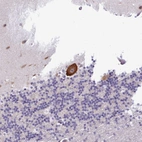

Immunohistochemical staining of human cerebral cortex shows strong cytoplasmic positivity in neuronal cells.